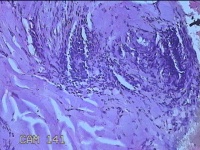

性别

男

年龄

41岁

临床诊断

皮脂腺痣

一般病史

双下肢红斑痒一年余。

标本名称

双下肢肿物

大体所见

灰白暗红色肿物0.8x07x0.3cm一个,表面糜烂。

图2